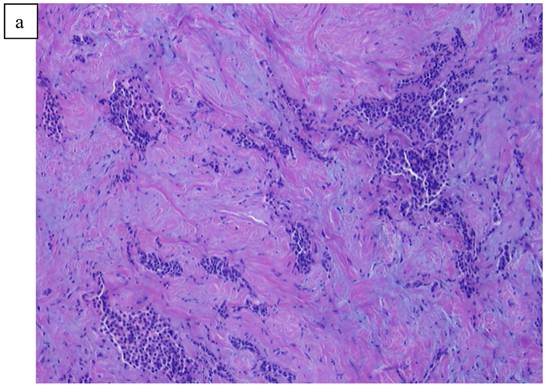

In Figure 1, we are able to discern two discrete lesions of the left breast the nature of which were defined by core biopsy. The initial core biopsies of all three lesions were performed in the mammography department of North Shore Univ Hospital. The right breast proved to have a solitary lesion demonstrating predominantly lymphocytic pathology consistent with a B cell lymphoma. In the left breast 2 separate pathologic processes were defined, one an infiltrating ductal carcinoma (Fig. 2a, 2b) and in close proximity, a second lesion, the B-cell lymphoma (Fig 3a, 3b). No further surgery was performed on the right breast. The left breast underwent partial mastectomy. Nodes that were sampled from the left axilla were all negative.

Figure 2

a). Poorly differentiated ductal Carcinoma obtained from a biopsy of the left breast carcinoma. b). High power view of the invasive ductal carcinoma obtained from the left breast x20.